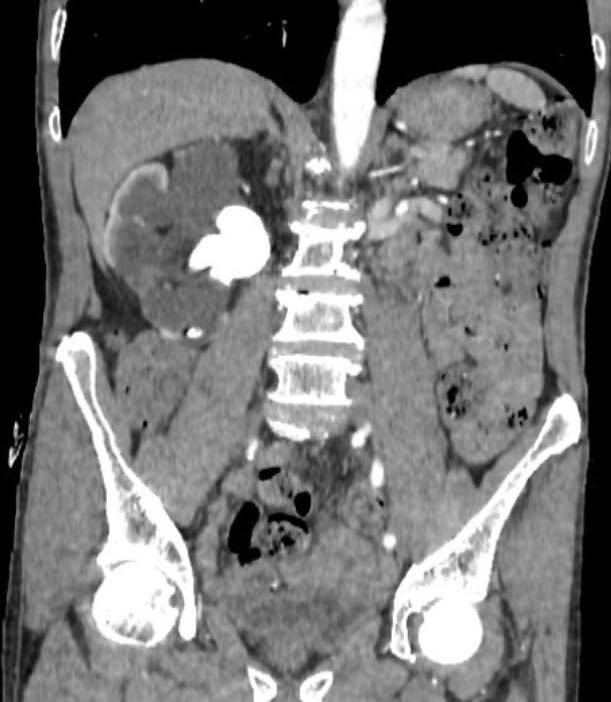

Tuy nhiên, thực tế lại hoàn toàn ngược lại. Rất nhiều bệnh nhân uống thuốc nam ròng rã suốt nhiều năm mà không thăm khám, không theo dõi tiến triển của bệnh. Trong khi đó, sỏi thận âm thầm phát triển, gây tắc nghẽn đường tiết niệu, làm thận giãn dần, suy giảm chức năng mà không gây ra triệu chứng rõ rệt.

Khác với những cơn đau quặn thận dữ dội dễ khiến người bệnh đi khám sớm, nhiều trường hợp sỏi thận diễn tiến lặng lẽ. Khi phát hiện thì thận đã mất chức năng, không còn khả năng hồi phục. Lúc này, giải pháp duy nhất là phẫu thuật cắt bỏ để tránh biến chứng nhiễm trùng, ảnh hưởng đến tính mạng.